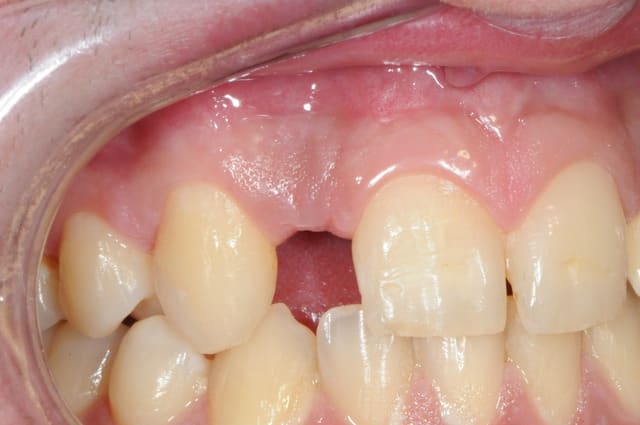

j'ai une photo de chir mais tu ne me feras pas croire que l'on peut mettre des implants là dedans!